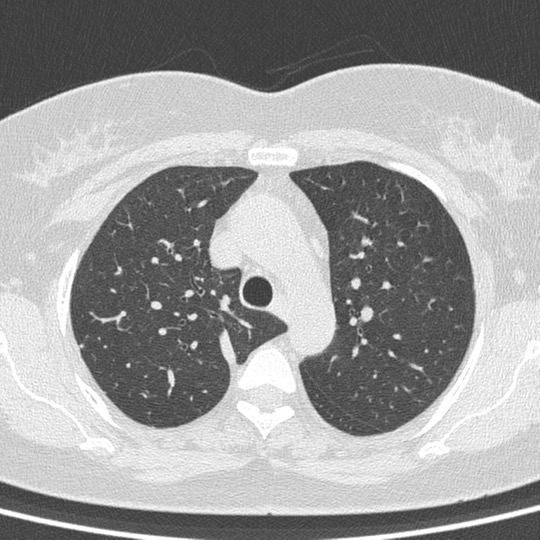

An Azygos lobe fissure is seen on right side. It extends from the lateral aspect of the vertebral body posteriorly, to the right brachiocephalicvein and SVC anteriorly.